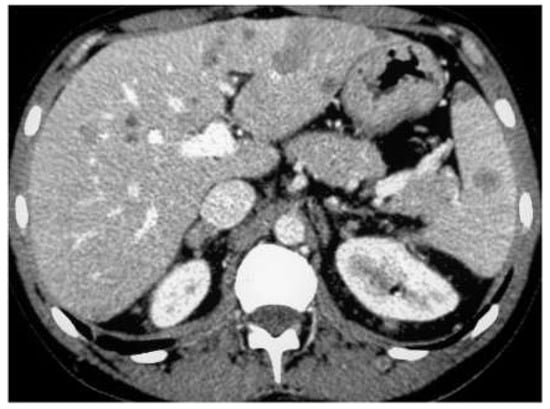

2.7. Solid Lesions